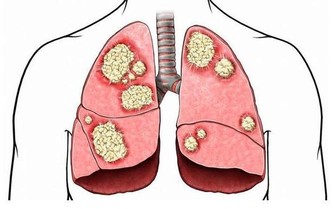

你知道嗎?在台灣,約有90%的民眾一生受一到兩次的便秘與痔瘡困擾,

而其中有近九成的痔瘡族,受限於工作、手術時間、恢復期等因素,

往往要等到痔瘡「大爆血」的嚴重程度才肯就醫治療。